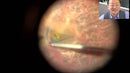

12-301-23 Gripping Vitreoretinal Forceps with a Sandblasted Platform, 23 Ga, Tip Only

SKU:12-301-23

€424,80 €531